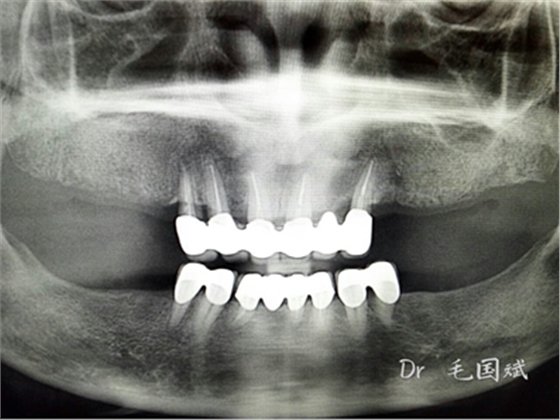

毛國(guó)斌種植病例——群討論分享